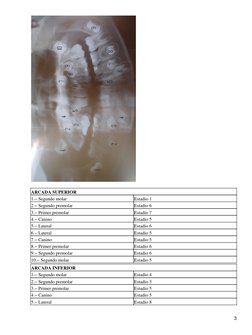

ARCADA SUPERIOR 1. Segundo molar 2. Segundo premolar 3. Primer premolar 4. Canino 5. Lateral 6. Lateral 7. Canino 8. Primer premolar 9. Segundo premolar 10. Segundo molar ARCADA INFERIOR 1. Segundo molar 2. Segundo premolar 3. Primer premolar 4. Canino 5. Lateral

Estadio 1 Estadio 6 Estadio 7 Estadio 5 Estadio 6 Estadio 5 Estadio 5 Estadio 6 Estadio 6 Estadio 5 Estadio 4 Estadio 3 Estadio 5 Estadio 5 Estadio 8

6. Canino 7. Primer premolar 8. Segundo premolar 9. Segundo molar CONCLUSIONES

Estadio 7 Estadio 6 Estadio 6 Estadio 6